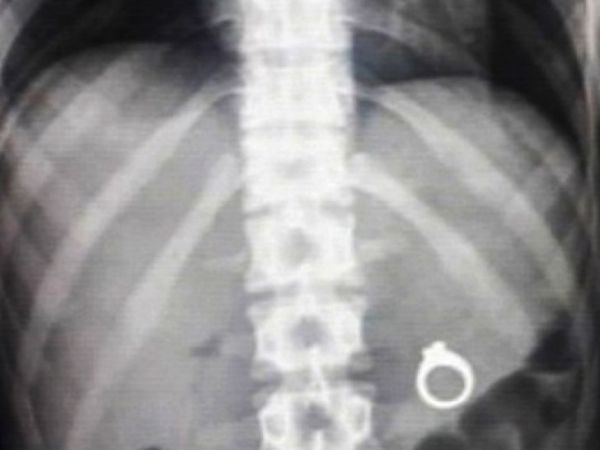

Многие мужчины хотят быть романтиками и сделать предложение своей половинке каким-нибудь необычным образом. И многие используют, к примеру, еду, чтобы спрятать там сюрприз в виде кольца. Так вот, мужчины, делайте предложение до того, как ваша суженая решит попробовать это блюдо с сюрпризом.